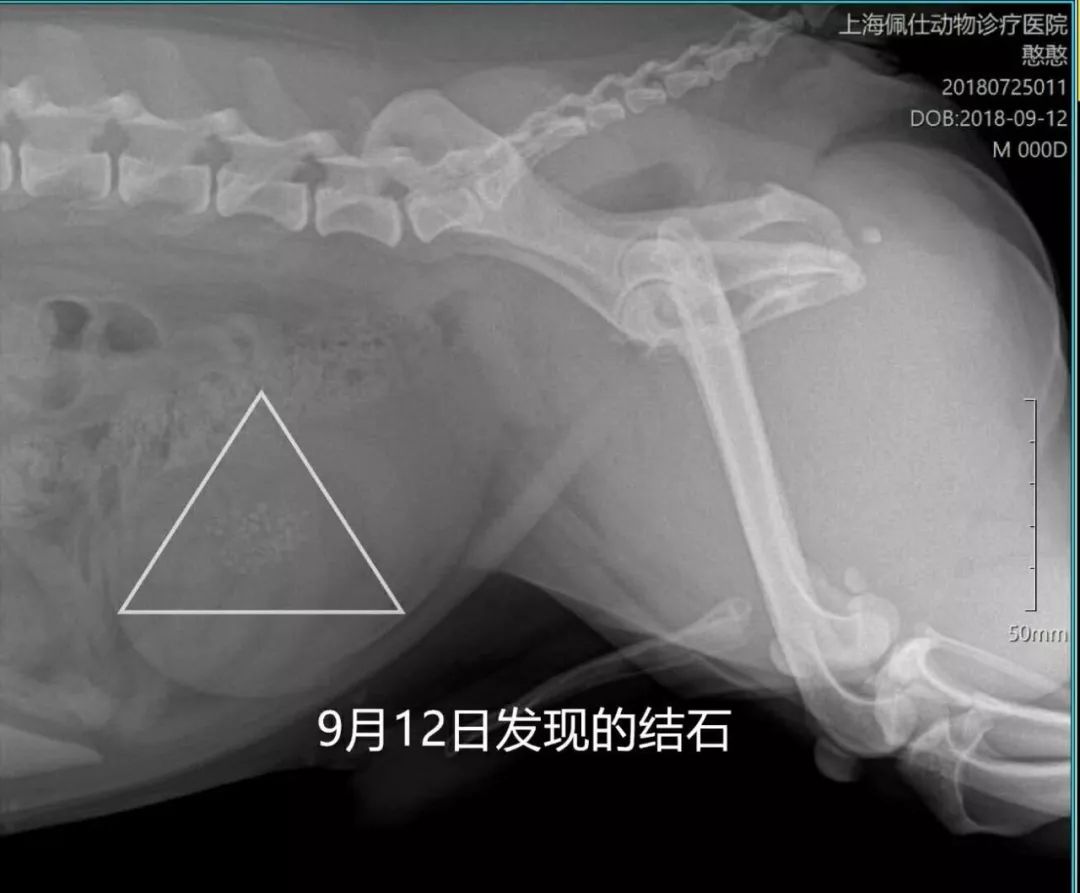

(图片为狗狗结石的照片)